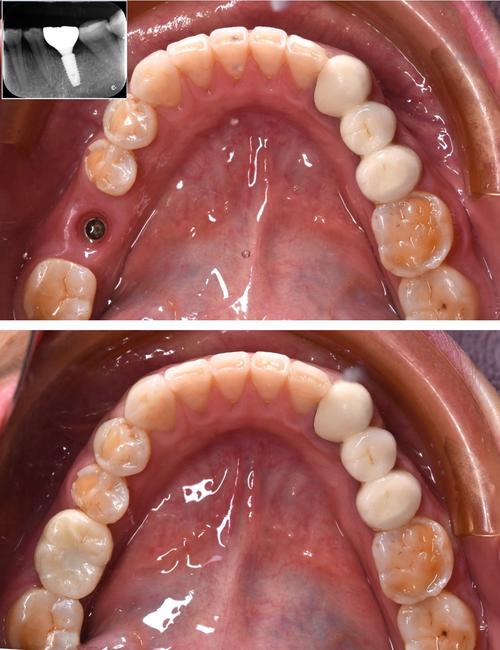

种植牙的完整流程通常包括术前评估、手术植入、骨结合、修复安装及后期维护五个阶段,术前评估是关键,需通过口腔检查、CBCT(锥形束CT)等影像学检查评估牙槽骨的骨量、密度及重要解剖结构(如下牙槽神经、上颌窦位置),同时排查全身性疾病,确保手术安全,手术阶段在局部麻醉下进行,医生会切开牙龈,逐级备洞后将种植体植入牙槽骨内,缝合伤口,整个过程约30分钟-2小时(根据种植数量复杂度而定),术后需服用抗生素预防感染,避免剧烈运动,1周左右拆线,骨结合期是种植成功的核心,种植体与牙槽骨通过新生骨组织直接连接,此期间需避免种植体受力,通常3-6个月(骨质差者可能需植骨,延长至6-9个月),骨结合完成后,安装愈合基台,让牙龈形成自然形态,2周后取模制作牙冠,最后戴牙冠并调整咬合,完成修复,后期维护同样重要,需定期复查(每年1-2次),保持口腔卫生,正确使用牙线、冲牙器,避免咬硬物,确保种植牙长期使用。